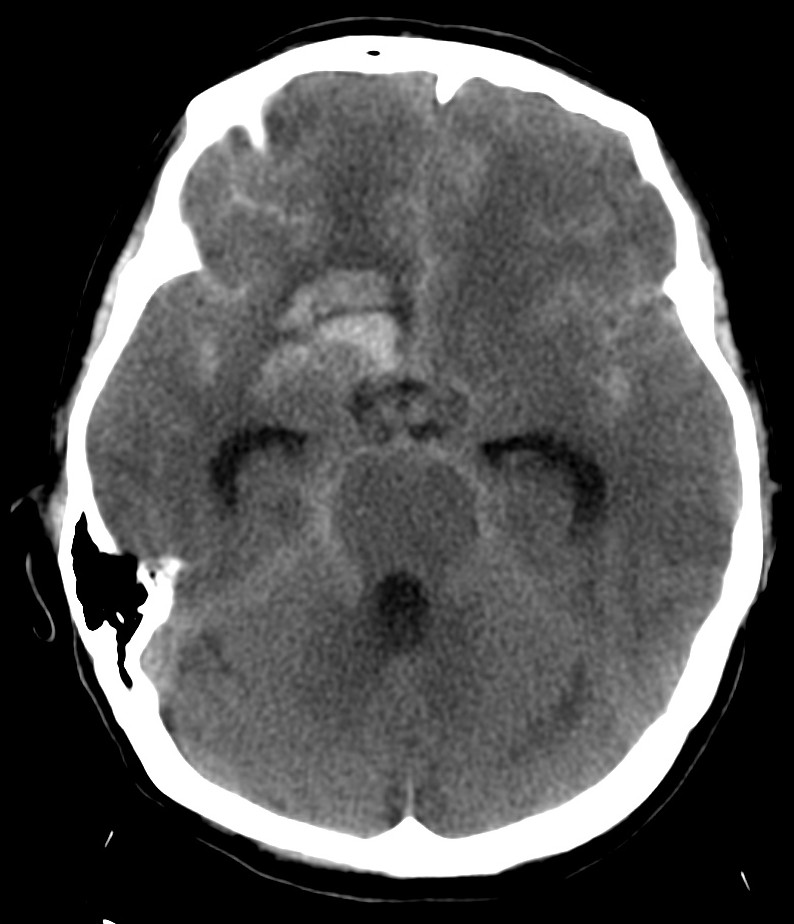

Se realiza TC de cráneo sin contraste, objetivándose:

Estamos ante una Hemorragia Subaracnoidea por rotura aneurismática.

Aunque la RM tiene mayor sensibilidad para el diagnóstico de sangrado, es la TC la prueba de primera línea debido a su mayor disponibilidad. Observaremos la característica imagen de hiperdensidad en las cisternas basales que corresponde a la sangre extravasada. La mayoría de las veces veremos el característico aumento de densidad alrededor del polígono de Willis (65%), que es donde ocurren la mayoría de las roturas de aneurismas, y también en la región de la cisura de Silvio (30%). Podemos ver también sangre en la fosa interpeduncular o asta occipital de los ventrículos laterales.